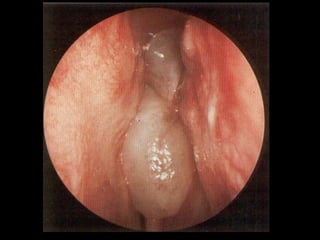

• Greyish pale glistening polypoidal mass can be seen through anterior

rhinoscopy. It is insensitive and doesn’t bleed on touch. It is soft and

mobile and can be probe all around except laterally.

• Pale grey colour is due to poor blood supply but, in the presence of

repeated trauma and inflammation, they may become reddened. The

insensitivity is due to poor nerve supply.

SIGNS • Patients havea distinctive hypo nasal voice. • Mouth Breathing. • Greyish pale glistening polypoidal mass can be seen through anterior rhinoscopy. It is insensitive and doesn’t bleed on touch. It is soft and mobile and can be probe all around except laterally. • Pale grey colour is due to poor blood supply but, in the presence of repeated trauma and inflammation, they may become reddened. The insensitivity is due to poor nerve supply. • Posterior Rhinoscopy : A Smooth Greyish Polypoidal mass occupying the choana – AC polyp. • A severe Eosinophilia may change the colour of the mucus from white to yellow or greenish yellow colour and was called allergic pus.